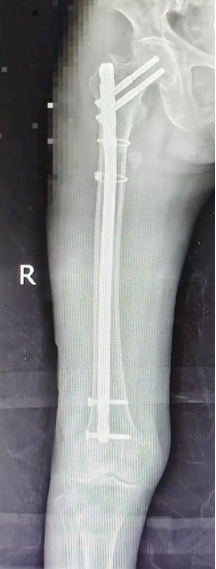

经多学科专家诊断:陈阿婆右股骨近端粉碎性骨折,并伴有肋骨骨折、胸腔积液和高血压——对高龄长者而言,任何一项都可能成为“致命一击”。在救治过程中既要应对骨折剧痛,又要控制高血压风险,同时要处理肋骨骨折与胸腔积液可能引发的呼吸问题。

会诊次日,在崔红旺主任带领下,创伤科手术团队为患者实施了微创内固定手术。专家们屏息凝神,在极小创伤下完成骨折精准复位与固定。一个多小时后,手术圆满成功——全程出血少、时间短,成功跨越高龄与多基础病的双重手术难关。

图片